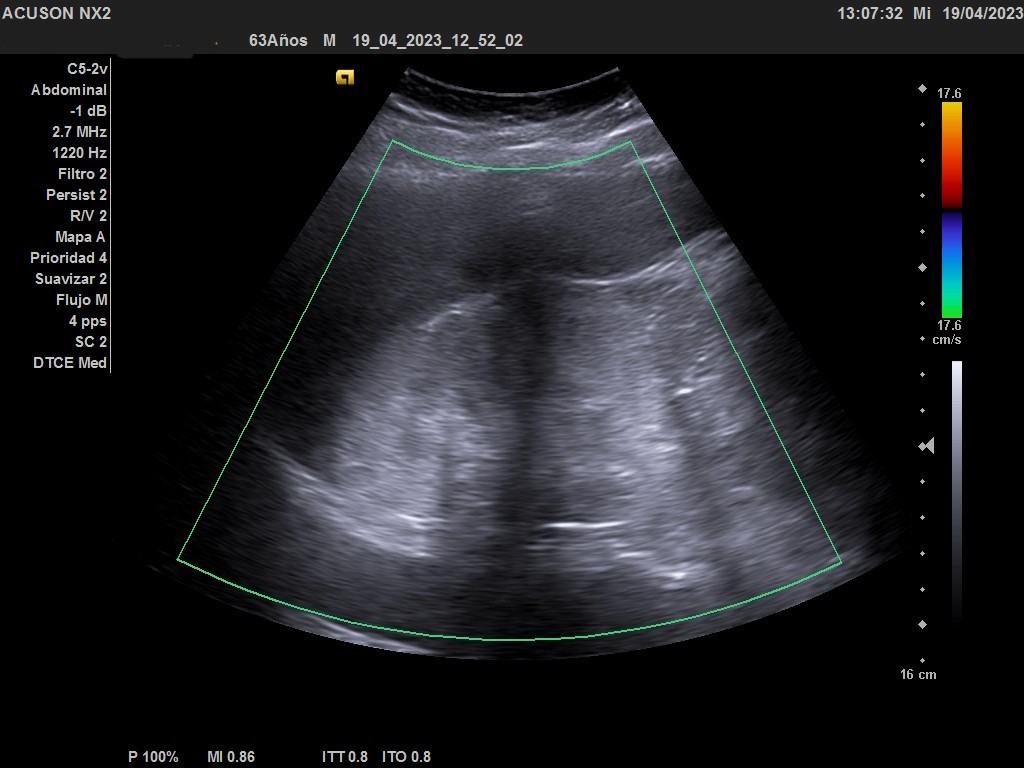

Hallazgos ecográficos

Ecografía clínica urológica: se observa imagen hiperecogénica a nivel de polo superior de riñón derecho que no capta al Doppler color y que mide 10 cm.